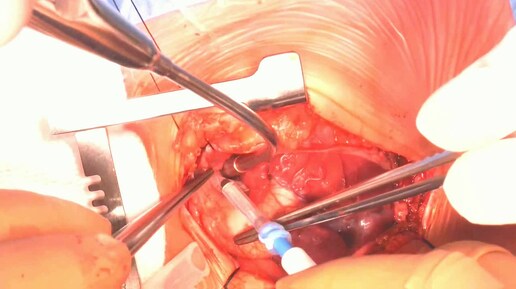

06:571,0×00:00/06:57Хирургическое лечение бактериального эндокардита при сочетанном поражении митрального и аортального клапанов5 месяцев назад